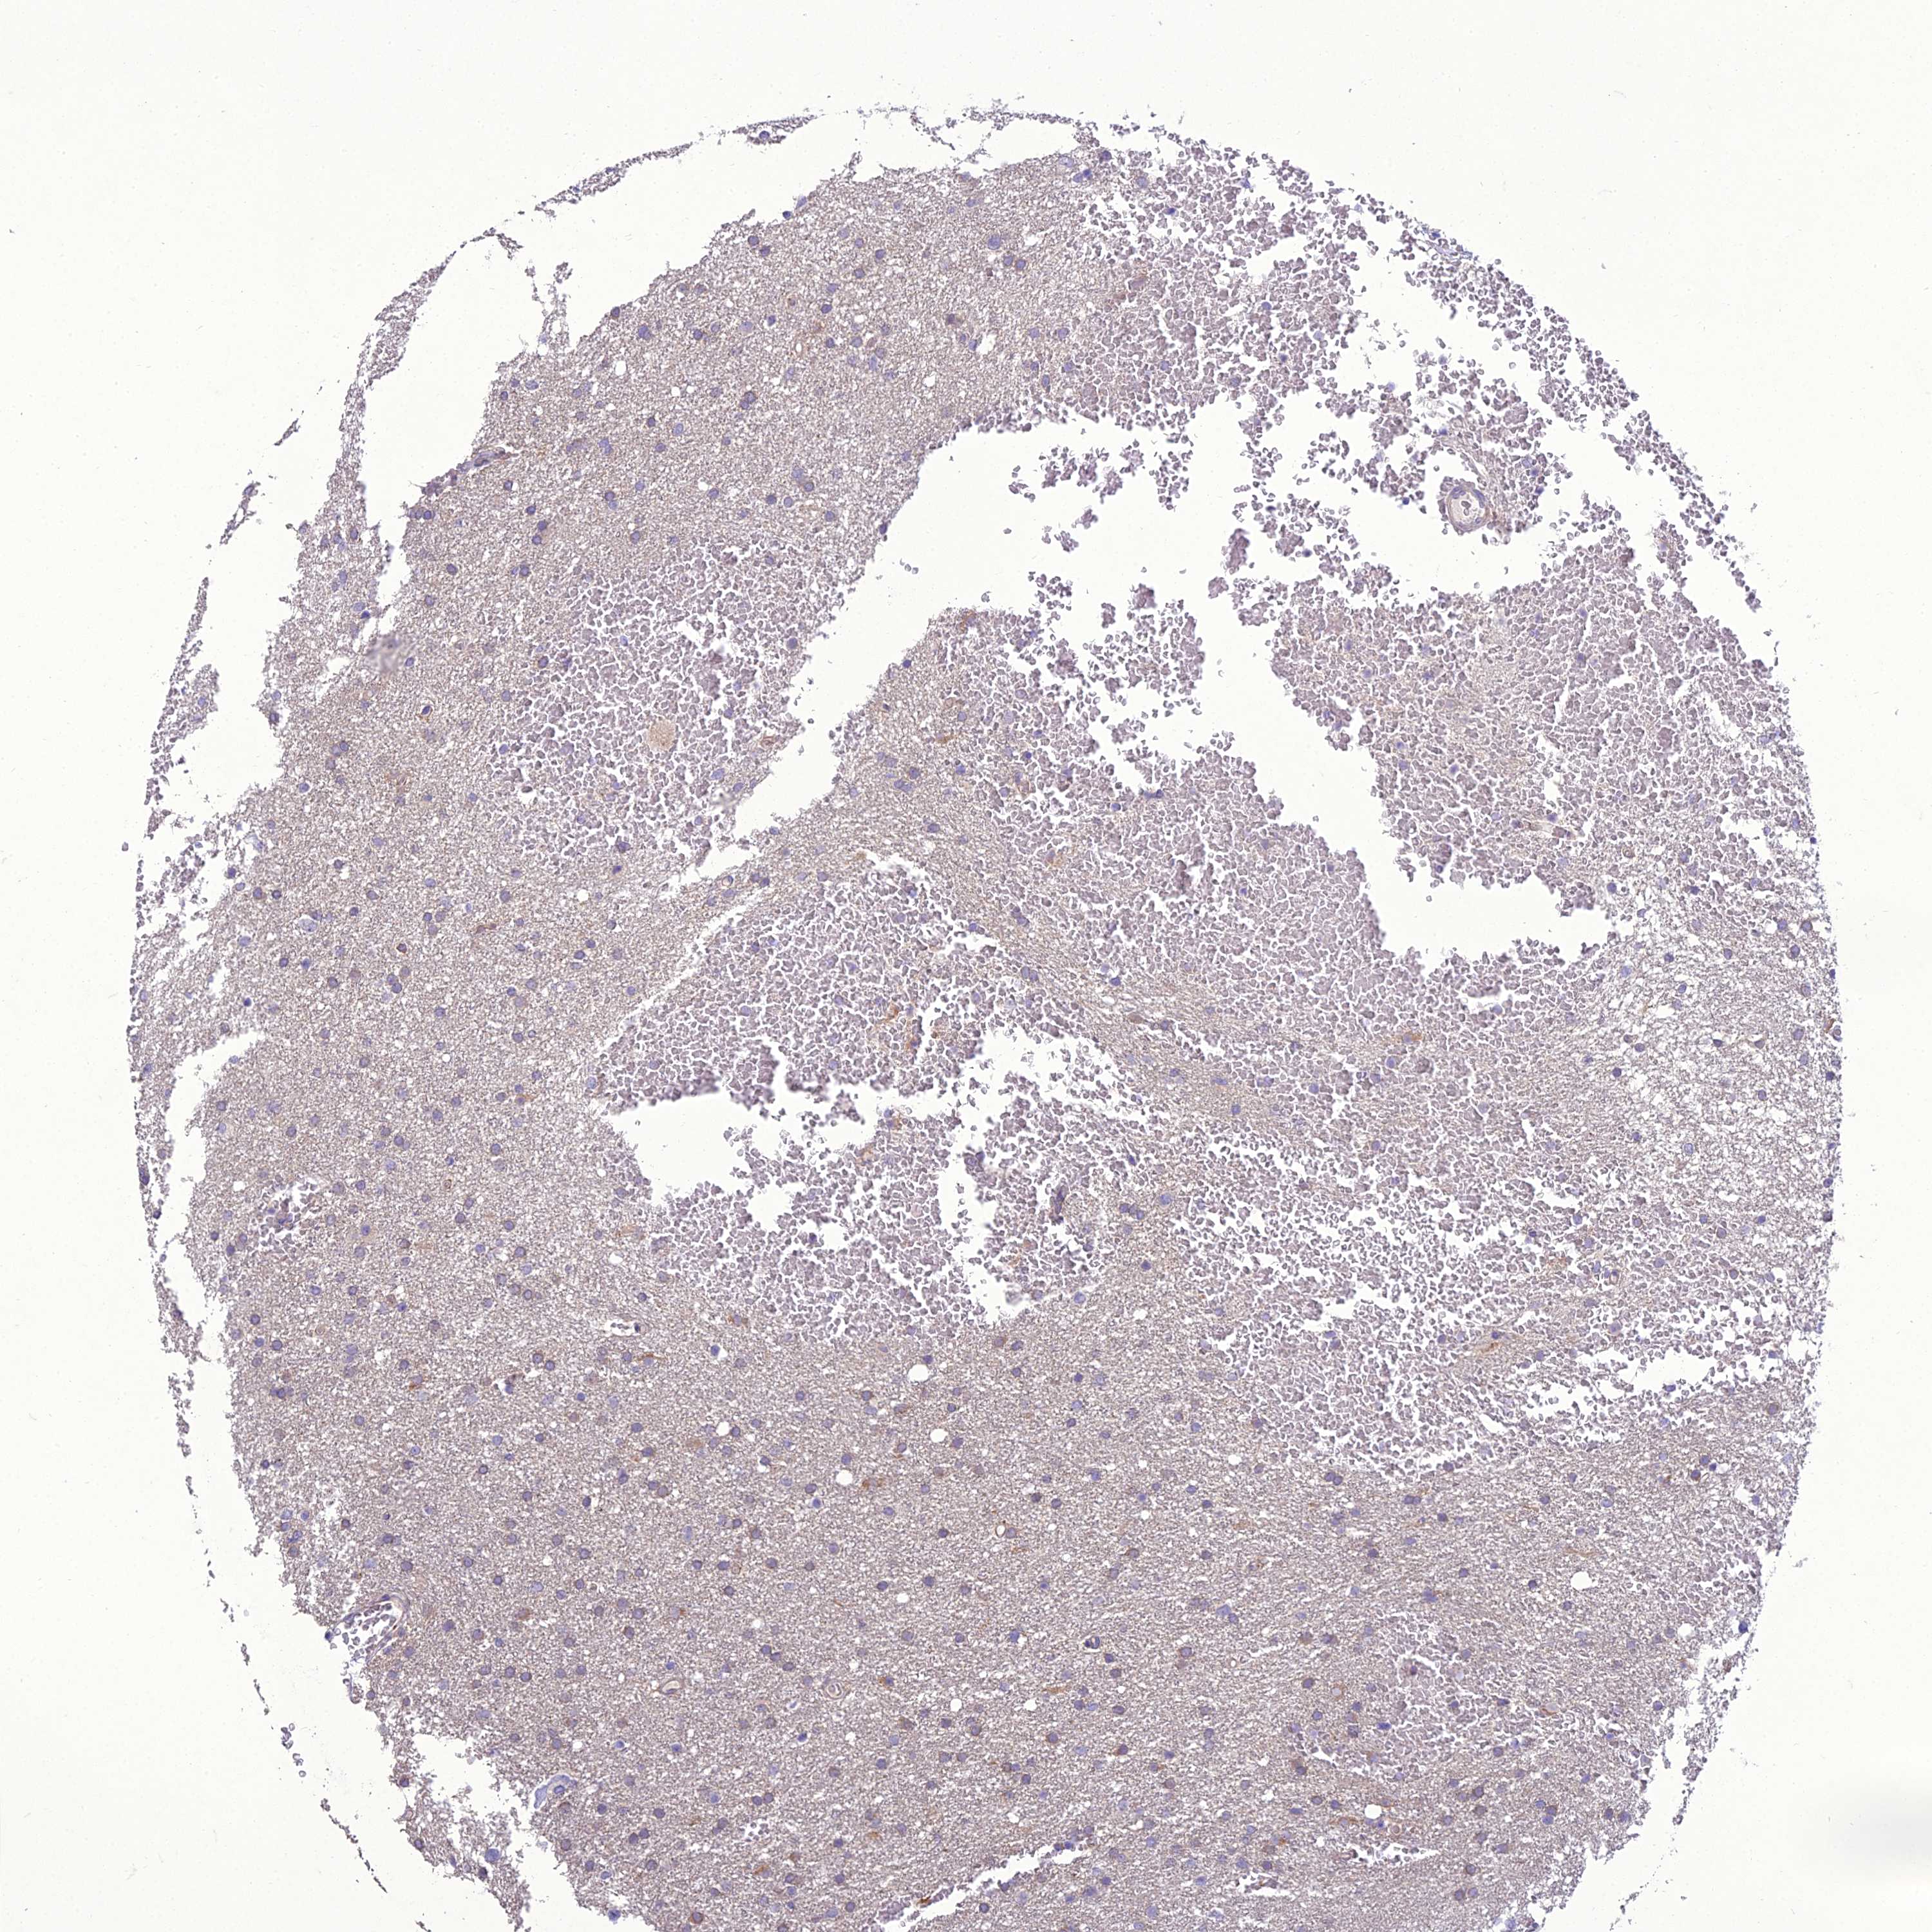

GLIOMA - Protein expressioni

A mouse-over function shows sample information and annotation data. Click on an image to view it in a full screen mode. Samples can be filtered based on level of antibody staining by selecting one or several of the following categories: high, medium, low and not detected. The assay and annotation is described here.

Note that samples used for immunohistochemistry by the Human Protein Atlas do not correspond to samples in the TCGA dataset.

Antibody stainingi

Antibody staining in the annotated cell types in the current human tissue is reported as not detected, low, medium, or high, based on conventional immunohistochemistry profiling in selected tissues. This score is based on the combination of the staining intensity and fraction of stained cells.

Each image is clickable and will lead to virtual microscopy that enables deeper exploration of all samples and also displays staining intensity scores, fraction scores and subcellular localization as well as patient and tissue information for each sample.

Antibody HPA043737

Staining

High

Medium

Low

Not detected

Intensity

Strong

Moderate

Weak

Negative

Quantity

>75%

75%-25%

<25%

None

Location

Nuclear

Cytoplasmic/membranous

Cytoplasmic/membranous,nuclear

Glioma, malignant, High grade

Glioma, malignant, Low grade